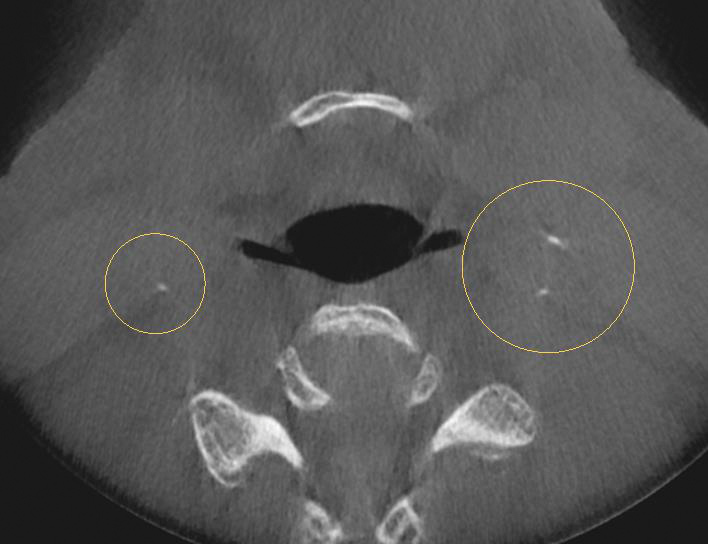

A comprehensive dental exam was performed that included a blood pressure test, an oral cancer screening, intraoral photographs, full mouth radiographs, a periodontal chart, a saliva test, and a CBCT scan. The exam confirmed the presence of active dental decay, periodontitis (ie, stage III, grade B), and areas of calcifications in his carotid artery (Figure 1 through Figure 3).

(1.) CBCT panoramic view.

Figure 1